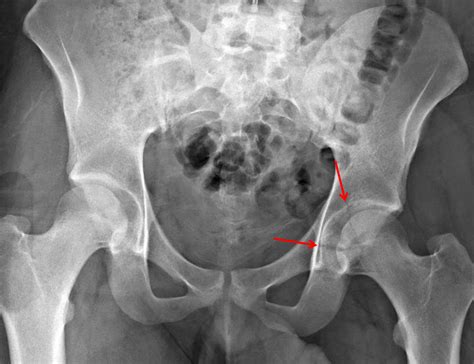

Posterior Column Fracture of the posterior column of the acetabulum

Diagnosis of Fractures of the Acetabulum

Diagnosing fractures of the acetabulum involves a combination of clinical examination and imaging studies. The diagnostic process typically includes:

• X-rays: Initial imaging to visualize the fracture pattern and assess the extent of the injury.